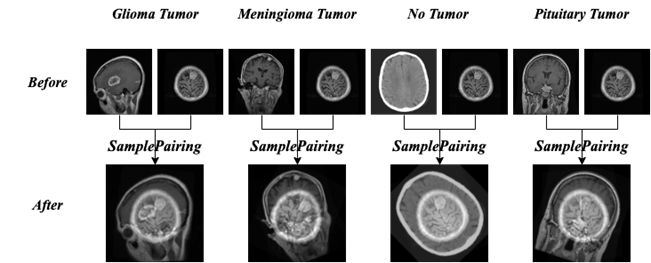

2.2.3 SamplePairing

The third algorithm is SamplePairing, which is based on the principle that two images are randomly selected from the training set and processed by the basic data enhancement operation respectively, and then superimposed by the pixels in the form of taking the average value to synthesize a new sample, labeled as one of the original sample labels. These two images are not restricted to the same category, this method is more effective for medical image processing. The specific process is shown in Fig. 5 and the specific effect is shown in Fig. 6.